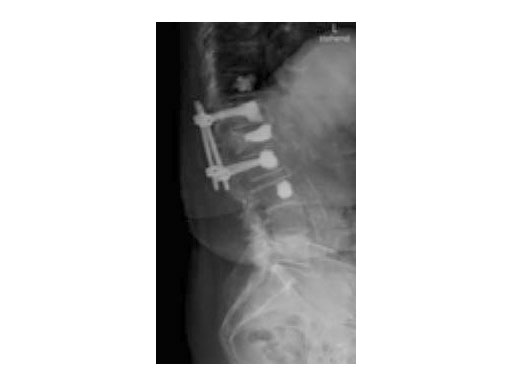

A 78-year-old woman was affected by steroid induced osteoporosis. She had persisting pain (mechanic and muscular) due to static imbalance (hyperkyphosis) and nonunion 8 months after a minor trauma with a vertebral compression fracture and vertebra plana of L1, and development of symptomatic stenosis of the spinal canal with loss of mobility over time. Pre-existing degenerative lumbar scoliosis was increased by the fracture.

A 76-year-old man was affected by advanced osteoporosis (SD -2.5) (alcohol, steroids).